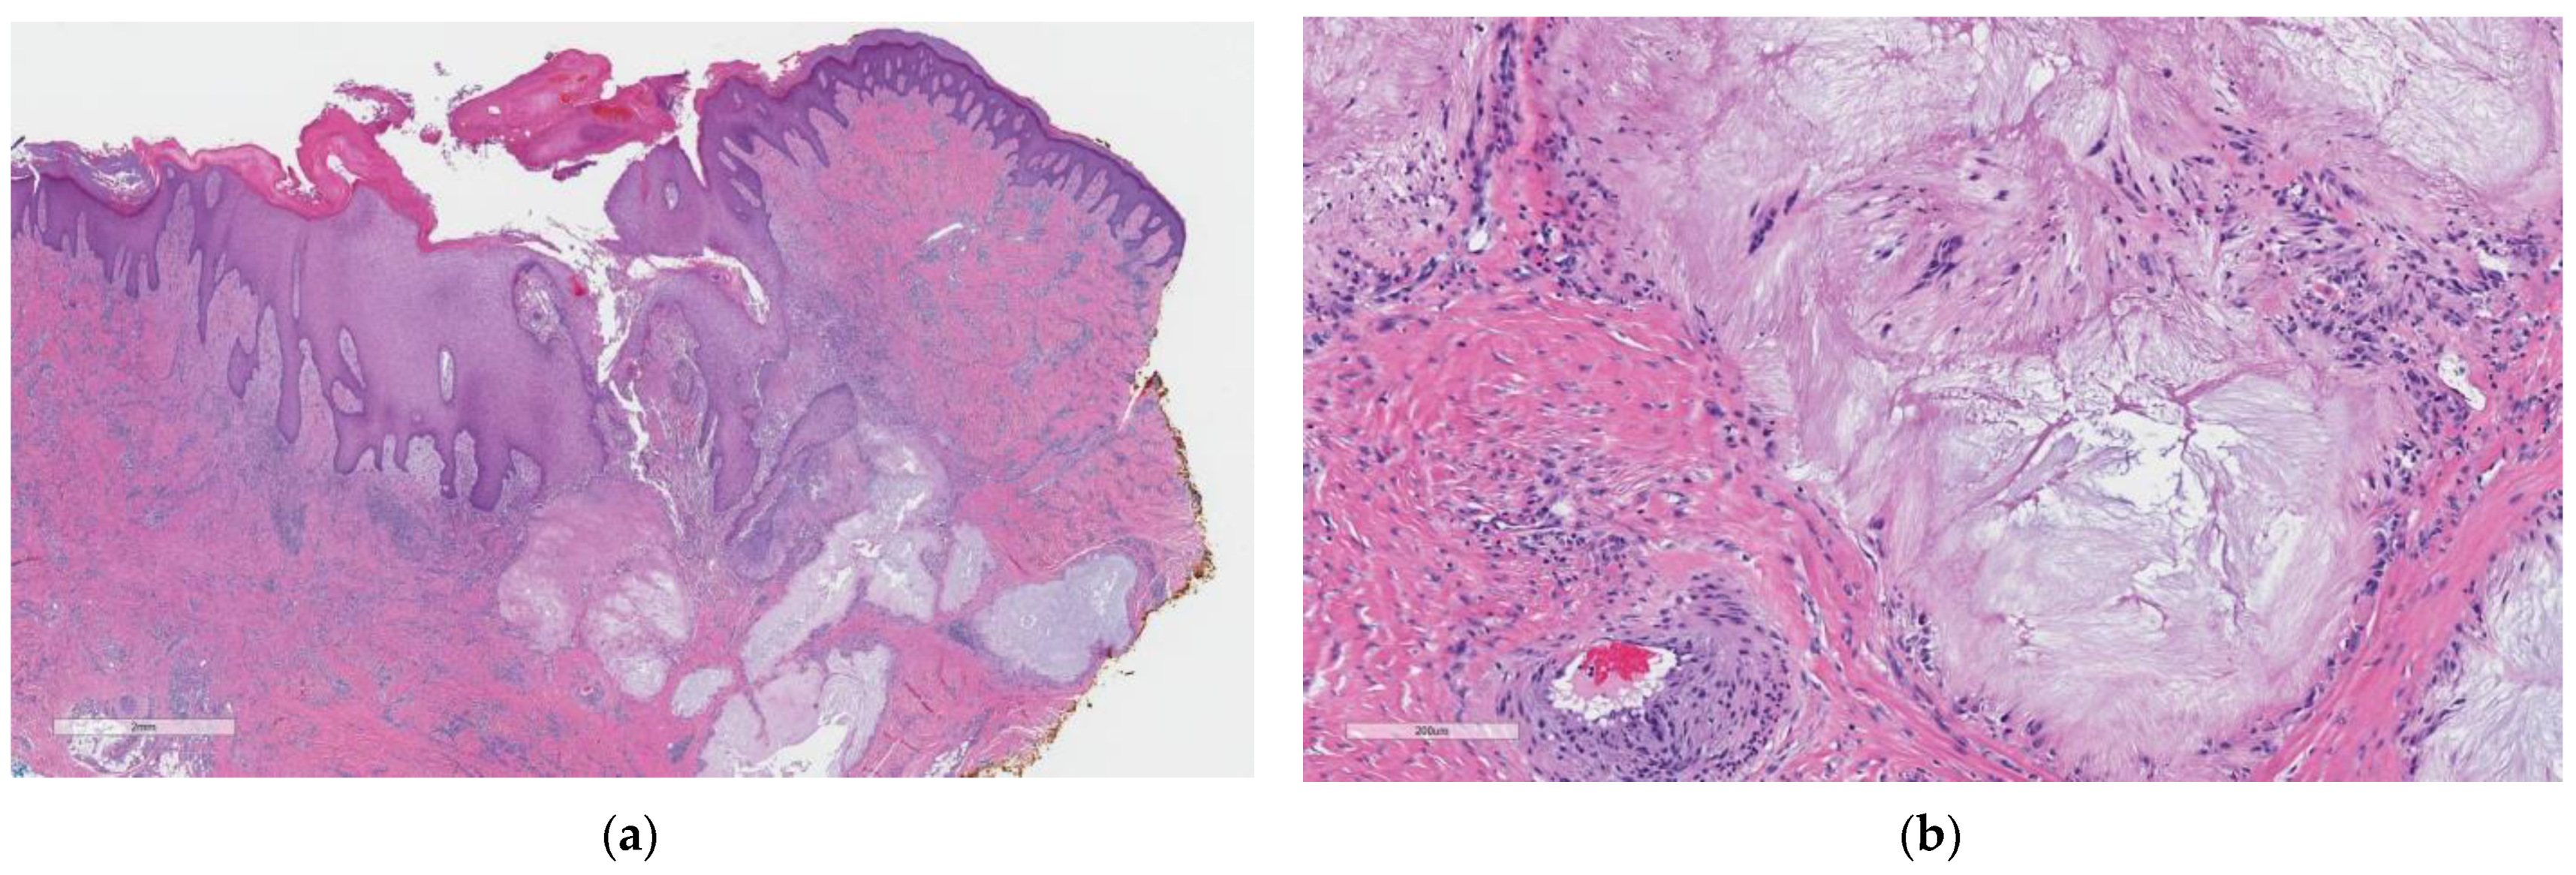

2. Case Report